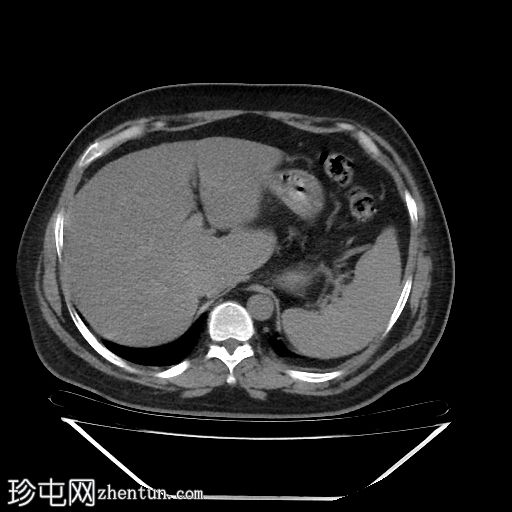

轴位增强扫描(门静脉期)

远端降结肠后壁可见一小(<15 mm)、局限性空腔,内含气泡,伴有不规则肠壁强化和轻度邻近肠系膜脂肪条索状改变。

未见脓肿、腹水、弥漫性气腹,提示IA期复杂性急性穿孔性憩室炎(局部穿孔)。

临床表现符合IA期复杂性急性穿孔性憩室炎(局部穿孔)。

患者目前接受保守治疗,使用广谱抗生素。